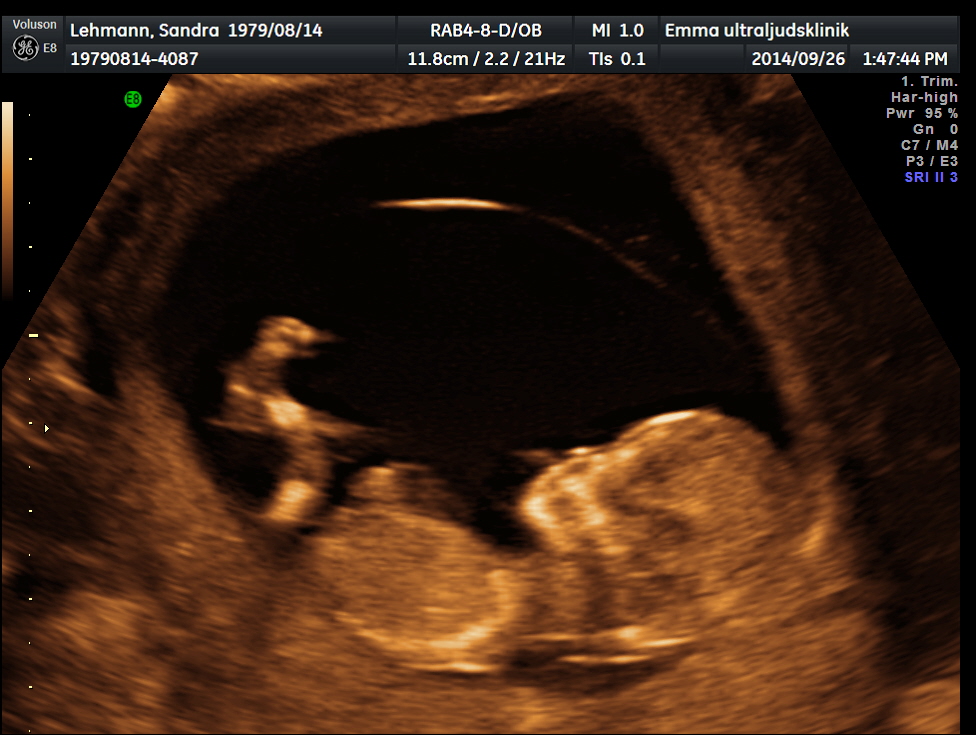

Ultraljudet var så spännande, och bilderna man fick. Man tittade sönder dem. Nu först tog jag upp bilderna och tittade på dem. Och vi var på ultraljudet för 6 veckor sedan.